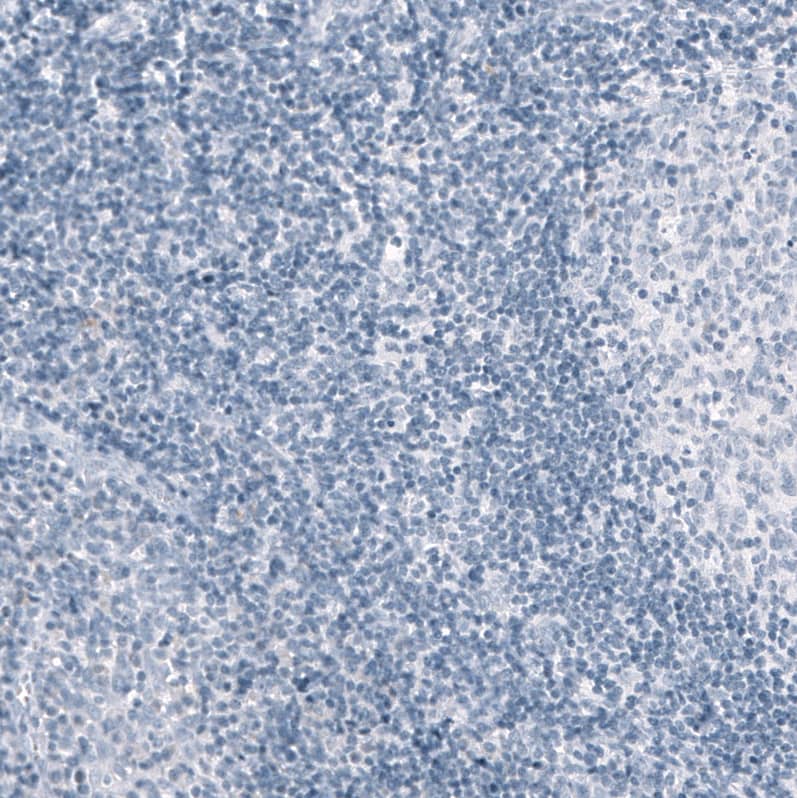

Immunohistochemistry-Paraffin: Osteopontin/OPN Antibody [NBP3-44052]

Staining of human cerebellum shows moderate cytoplasmic positivity in microglia.Immunohistochemistry-Paraffin: Osteopontin/OPN Antibody [NBP3-44052]

Staining of human cerebral cortex (Alzheimer disease) shows moderate cytoplasmic positivity in microglia.Applications for Osteopontin/OPN Antibody (CL10686) - Azide and BSA Free